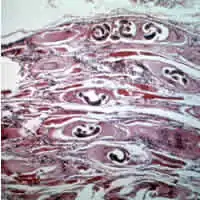

Jednotlivé druhy se liší ve své patogenitě, spektru hostitelů a rozšíření. Dospělé pohlavně zralé trichinely (tj. svalovci) žijí ve střevě. Samci měří 1–1,8 mm, samice 1,3–3,7 mm. Larvy v kapsulách ve svalovině jsou dlouhé až 1,3 mm.

- biopsie ze svalů – nález larev.